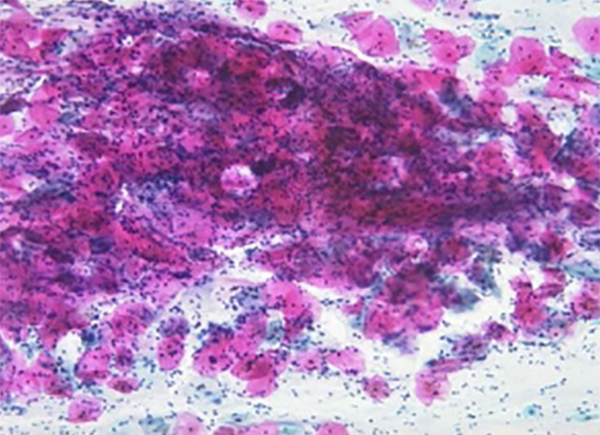

Dünnschichtzytologie, Monolayer, Flüssigkeitszytologie

Schon der bisherige Krebsabstrich bringt ein hohes Mass an Sicherheit bei der Früherkennung der Vorstadien des Gebärmutterhalskrebses. Es sind technische Gründe, die bei diesem Verfahren einen kleinen Prozentsatz an Unsicherheit übrig lassen.

Ein neues und aufwändiges Verfahren des Vorsorge-abstriches kann dieses Risiko noch weiter reduzieren. Das Verfahren wurde in den USA entwickelt und steht jetzt auch hier zur Verfügung.

Dabei wird aus dem Gebärmutterhals Zellmaterial gewonnen und automatisiert nach im Dünnschicht-